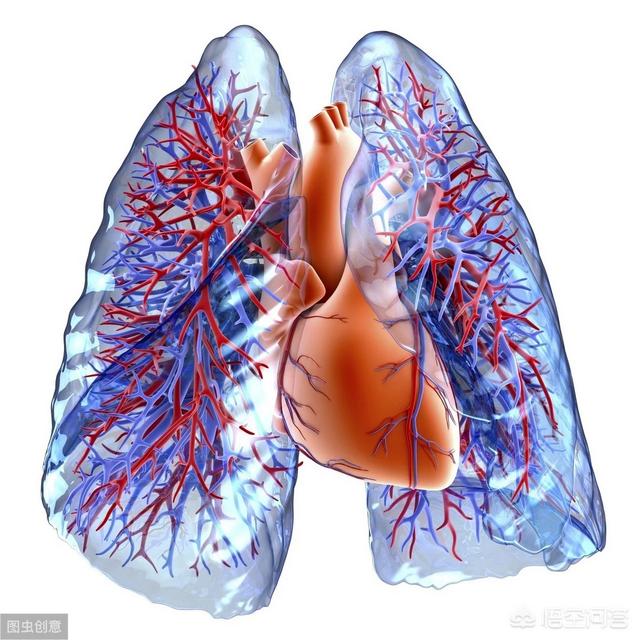

如图所示,红色的是肺静脉,因为含有丰富的氧气,肉眼呈鲜红色(动脉血);蓝色的是肺动脉(静脉血)。